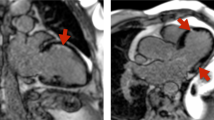

The rats were divided into four groups. Group 1, controls, was not given ADR or CARN. Group 2 was given ADR (15 and 20 mg/kg, respectively, cumulative dose) by two and four i.p. injections for 1 and 2 wk. Group 3 was given the same dose of ADR and supplemented with CARN (200 mg/kg). Group 4 was given CARN (200 mg/kg). Cardiomyopathy was induced in groups 2 and 3 by i.p. injection of ADR hydrochloride (doxorubicin hydrochloride, cumulative dose, 5, 10, 15, and 20 mg/kg) for a 2-wk period. CARN (200 mg/kg) was administered by i.p. injection daily for a 2-wk period. The volume of ADR injected was 1.25 mL/kg, and that of CARN, 1 mL/kg. The rats were weighed and observed for general appearance, behavior, and mortality during the study period. They were also assessed for clinical evidence of ascites, limb edema, and abnormal fur characteristics at the time of each injection and before sacrificing. At the toxic dose of ADR (15 and 20 mg/kg), congestive heart failure was seen in affected rats with notable tachypnea and ascites. Increased heart weight and internal ventricular dimensions were demonstrated at autopsy. Irregularly arranged myofibrils, markedly swollen mitochondria, nuclear fragmentation, and chromatin clumping were found by electron microscopy, and apoptosis was confirmed by a nick-end labeling method (19).

Figure 1 shows the effect of CARN on heart tissue CPT I and CPT II activity at different doses in ADR-treated rat with and without CARN (Tables 1 and 2). After attaining a cumulative dose of 15 mg (Table 1) and 20 mg (Table 2), ADR caused a significant inhibition of the activity of heart CPT I and CPT II. ADR induced a 44% decrease of CPT I and a 32% decrease of CPT II at a cumulative dose of 15 mg (Table 1). There was a 67% decrease of CPT I and a 23% decrease of CPT II at a cumulative dose of 20 mg (Table 2).

The addition of CARN did not reverse the ADR-induced inhibition of CPT I and CPT II activity. Surprisingly, the activities of both CPT I and CPT II were further decreased when CARN was supplemented to the ADR. However, in rats supplemented with CARN alone, the activities of both CPT I and CPT II were significantly elevated, being 48 and 65% greater than the control rats (Tables 1 and 2, and Fig. 1).